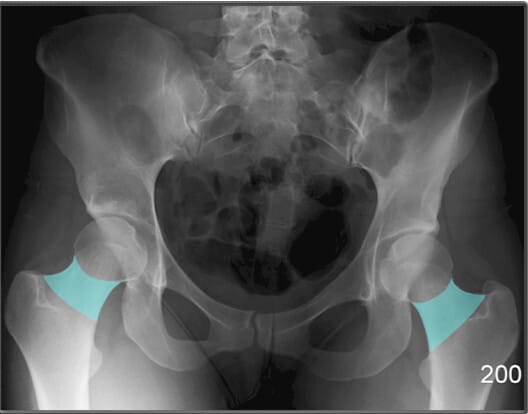

좌골결절 (Ischial Tuberosity)

| 좌골결절 (Ischial Tuberosity) |

| ✅ ‘앉는 뼈’라고도 불리는 부위로, 체중이 걸리는 지점입니다. AP pelvis 영상에서 골반의 가장 하단에 큰 음영으로 보입니다. |

| 🔴 햄스트링 기시부위로 근육 손상 및 견열골절이 발생할 수 있는 부위입니다. |